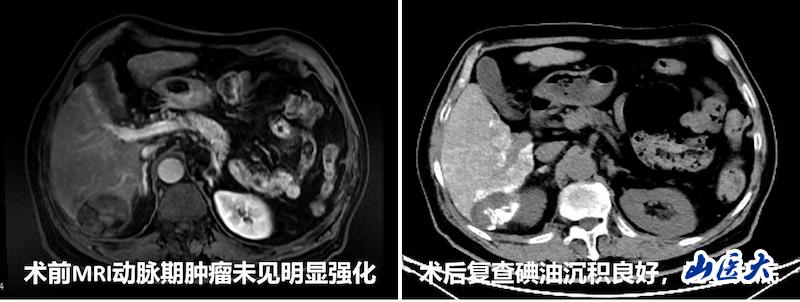

手术过程中,在CBCT的实时引导下,团队精准锁定患者肿瘤的三支供血动脉,并利用微导管逐一超选至目标血管,顺利完成化疗栓塞。栓塞后造影显示肿瘤血管完全消失,病灶碘油沉积良好。术后一周复查CT,碘油沉积范围与PET/CT提示的活性病灶范围完全一致,治疗效果明显。